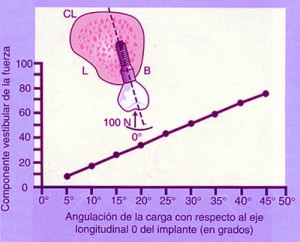

REF: SEGUNDA ENTREGA DEL CURSO: ANATOMÍA OCLUSAL INDIVIDUAL — ABBUTMENTS ANGULADOS POR IMPLANTES INCLINADOS Las piezas dentarias presentan un diseño biomecánico que a partir de su perpendicularidad a la Espiral Dinámica (Willams Mc Horris .Visión tridimensional de la Curva de Spee y de la Curva de Wilson.) reciben las fuerzas de manera axial al hueso receptor. Aplicando técnicas de análisis tridimensionales de elementos finitos y métodos fotoelásticos se ha podido comprobar que cuando se aplican cargas anguladas se producen grandes tensiones a nivel de la cresta ósea.(Misch). (Tomado de Misch) Con una angulación entre 0º y 15 º del abuttment la concentración de tensiones en la zona de la cresta es similar. — ALTURA DE LA CORONA Otro concepto importante es la Relación Corono – Implantaria. Sabemos que debido a la pérdida en altura del hueso es frecuente observar que el largo coronario supera el largo de la implantación endo ósea, situación que es según Misch, mas comprometida en importancia a la de la angulación del abbutmentt , provocando mayores reabsorciones crestales en el caso de recibir fuerzas no axiales. De la misma manera que en la oclusión dentaria, esta situación es manejable en Implantología actuando de manera axial sobre la pieza implantada o dentaria para que las fuerzas recaigan sobre el eje implantario o dentario. En ese sentido es importantísima la situación de los Contactos Interoclusales de manera Tripódica para mantener la Axialidad y sobre todo la Estabilidad de la Oclusión supra Implantes. Misch encuentra útil utilizar coronas de baja Altura Cuspídea incrementando el surco central dos o tres milímetros, con lo cual desde mi punto de vista no solo se disminuye la Eficacia Masticatoria, sino que se acerca al concepto de Céntrica Larga lo que a mi juicio incrementa el juego muscular e induce al Bruxismo.- En cuanto al contorno coronario, debido a que la mayoría de los Implantes tienen una plataforma menor en su emergencia que la que presentan la piezas naturales, es lógico reducir dichos contornos para evitar atrapamiento de alimentos y lograr una correcta fisioterapia natural de la encía peri implantaria. Es por eso la “Premolarización “ un recurso adecuado ya que recordemos que un premolar contiene en su estructura Oclusal la mitad de los componentes anatómicos de un molar los que aún así, cumplen con los conceptos de una OCLUSIÓN ORGANIZADA. REF: SEGUNDA ENTREGA DEL CURSO: ANATOMÍA OCLUSAL INDIVIDUAL Lo importante es que la plataforma del Implante se encuentre debajo de la resultante de las fuerzas axiales. Como dijimos es fundamental relacionar la anchura coronaria con el diámetro de la plataforma del Implante.(Misch). Crestas Estrechas Crestas Estrechas Premolarización Sin embargo si se tiene en consideración el Área Funcional Oclusal (de punto de contacto A a punto de contacto C (45% de su ancho total coronario), observaremos que la reducción coronaria en sentido vestibulo lingual o palatino, no altera la Eficacia Masticatoria ya que las áreas coronarias periféricas a la zona funcional solo sirven para conducir el alimento hacia la inserción del Implante produciendo el masaje fisiológico del alimento , y como la superficie de emergencia es menor que en un diente, lo que se conserva es la parte auténticamente necesaria y funcional de la cara oclusal. Funcionalidad Molar en el Plano Frontal REF: SEGUNDA ENTREGA DEL CURSO: ANATOMÍA OCLUSAL DE CONJUNTO EN EL PLANO FRONTAL Para obtener Axialidad en hueso Div. A es preciso conservar perpendicularidad entre el Implante y la Fosa Central de la Corona, pero a mi juicio, eso solo debe tener una recepción de la carga mediante puntos de contacto equilibrados preferentemente Tripódicos, ya que es el Tripodismo el esquema mecánico básico de estabilidad en la Física Mecánica. En el hueso Div . B –C y D ese eje debe lingualizarse dado el sentido de la reabsorción que se produce. (Tomado de Misch) Oclusion implanto asistida 1ª parteBinderman en un estudio de elementos finitos realizado en la década del 70, concluyó que todos los diseños de Implantes estudiados soportaban menor tensión si la carga era axial al eje mayor del Implante.

A partir de 15º estas tensiones se incrementan en un 50 % o más en la zona vestibular.